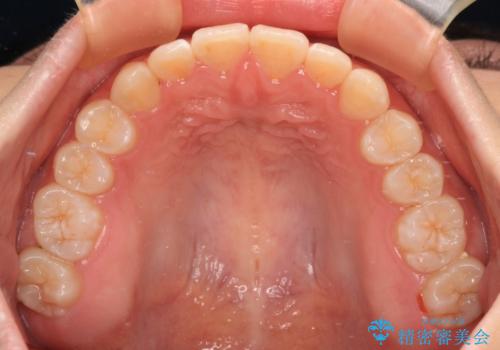

前歯のデコボコを整える インビザラインによる矯正治療

- 上下前歯のデコボコを気にして来院された患者様です。

叢生は軽度であり、ワイヤー矯正でもマウスピース矯正でも対応可能であったので、好きな装置を選んでもらいました。

相談の結果、インビザラインによる矯正治療を行うこととしました。

毎日の装着時間をしっかりと守っていただいたことで、1年程度で無事に治療を終えることができました。